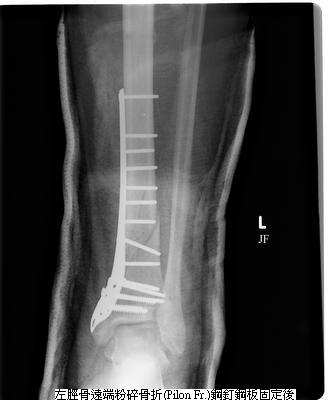

骨折開刀,用來固定的鋼釘、鋼板【(泛稱);目前用的都是合金材質】,在骨折癒合後,要不要拿掉?

早期骨科教科書或老師都說:骨折在癒合後,這些內固定金屬都應該要拿掉(取出)。要拿掉,最大的理由是:這些金屬對身體言 是不能吸收的「異物」,異物的存在,在身體免疫力變差時,有潛在會變成感染病灶的可能;另者,鋼釘、鋼板有的在骨折癒合後,會形成局部組織空間的擠壓或造成刺激,甚至使表皮、軟組織潰瘍;另外,有些情況,像鋼釘穿入關節腔,會妨礙關節活動、造成軟骨磨損,導致骨關節炎;而金屬也在作核磁共振或電腦斷層檢查時,會造成影像的干擾…..;這些,都是存留鋼釘鋼板可能有的不良後果,因此把鋼釘鋼板拿掉,邏輯上,好像是房子蓋好就把膺架拆除一樣,看似很自然的事。但”拿掉”也意味著還要再開一次刀,對病人言是要再面對一次麻醉與手術的風險,也須再付出醫療成本。 那麼,鋼釘鋼板是不是一定要拿呢?